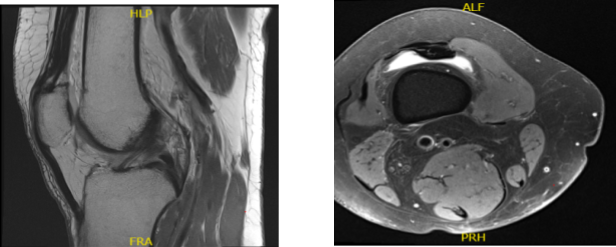

A 68  year-old female patient was seen in the office with right knee pain at Mather hospital and put in a knee brace and referred to us. MRI were reviewed and discussed by the doctor; Complex tear of the medial meniscus.

Mild MCL sprain superimposed on chronic scarring. Moderate chondromalacia patella and mild cartilage loss in the medial compartment. Moderate joint effusion.

MRI Right Knee Non-contrast